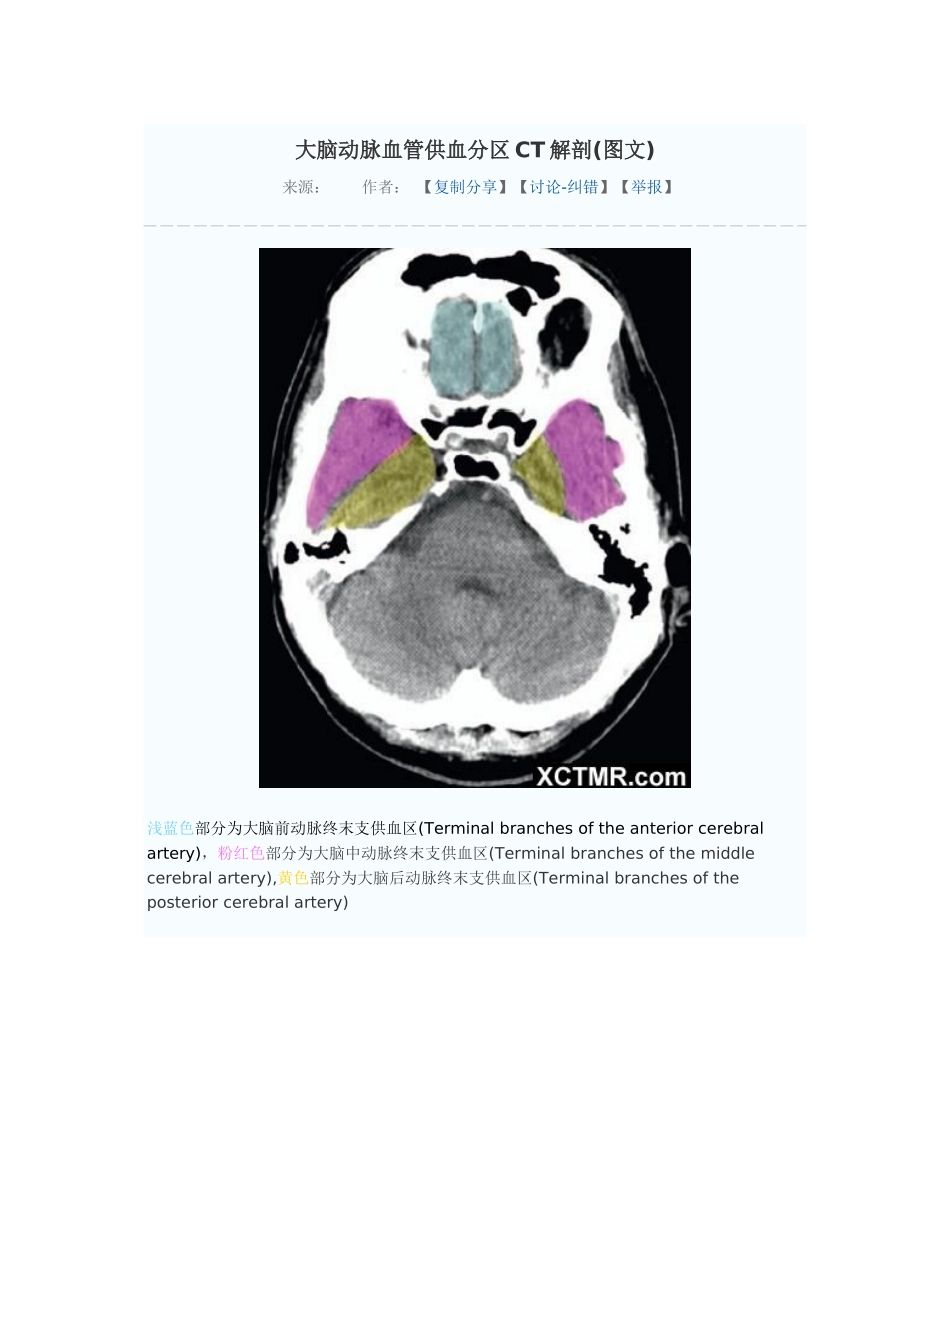

大脑动脉血管供血分区CT解剖(图文)来源:作者:【复制分享】【讨论-纠错】【举报】浅蓝色部分为大脑前动脉终末支供血区(Terminalbranchesoftheanteriorcerebralartery),粉红色部分为大脑中动脉终末支供血区(Terminalbranchesofthemiddlecerebralartery),黄色部分为大脑后动脉终末支供血区(Terminalbranchesoftheposteriorcerebralartery)浅蓝色部分为大脑前动脉终末支供血区(Terminalbranchesoftheanteriorcerebralartery),粉红色部分为大脑中动脉终末支供血区(Terminalbranchesofthemiddlecerebralartery),黄色部分为大脑后动脉终末支供血区(Terminalbranchesoftheposteriorcerebralartery),绿色部分为脉络膜前动脉供血区(Anteriorchoroidalartery),浅蓝色部分为大脑前动脉终末支供血区(Terminalbranchesoftheanteriorcerebralartery),粉红色部分为大脑中动脉终末支供血区(Terminalbranchesofthemiddlecerebralartery),黄色部分为大脑后动脉终末支供血区(Terminalbranchesoftheposteriorcerebralartery),绿色部分为脉络膜前动脉供血区(Anteriorchoroidalartery),褐色部分为大脑前动脉深穿支供血区(Penetratingbranchesoftheanteriorcerebralartery),枣红色部分为大脑后动脉深穿支及后交通动脉供血区(Penetratingbranchesoftheposteriorcerebralarteryandposteriorcommunicatingartery),浅蓝色部分为大脑前动脉终末支供血区(Terminalbranchesoftheanteriorcerebralartery),粉红色部分为大脑中动脉终末支供血区(Terminalbranchesofthemiddlecerebralartery),黄色部分为大脑后动脉终末支供血区(Terminalbranchesoftheposteriorcerebralartery),绿色部分为脉络膜前动脉供血区(Anteriorchoroidalartery),褐色部分为大脑前动脉深穿支供血区(Penetratingbranchesoftheanteriorcerebralartery),枣红色部分为大脑后动脉深穿支及后交通动脉供血区(Penetratingbranchesoftheposteriorcerebralarteryandposteriorcommunicatingartery),亮红色部分为大脑中动脉深穿支供血(Penetratingbranchesofthemiddlecerebralartery)浅蓝色部分为大脑前动脉终末支供血区(Terminalbranchesoftheanteriorcerebralartery),粉红色部分为大脑中动脉终末支供血区(Terminalbranchesofthemiddlecerebralartery),黄色部分为大脑后动脉终末支供血区(Terminalbranchesoftheposteriorcerebralartery),绿色部分为脉络膜前动脉供血区(Anteriorchoroidalartery),枣红色部分为大脑后动脉深穿支及后交通动脉供血区(Penetratingbranchesoftheposteriorcerebralarteryandposteriorcommunicatingartery),亮红色部分为大脑中动脉深穿支供血(Penetratingbranchesofthemiddlecerebralartery)浅蓝色部分为大脑前动脉终末支供血区(Terminalbranchesoftheanteriorcerebralartery),粉红色部分为大脑中动脉终末支供血区(Terminalbranchesofthemiddlecerebralartery),黄色部分为大脑后动脉终末支供血区(Terminalbranchesoftheposteriorcerebralartery),枣红色部分为大脑后动脉深穿支及后交通动脉供血区(Penetratingbranchesoftheposteriorcerebralarteryandposteriorcommunicatingartery),亮红色部分为大脑中动脉深穿支供血(Penetratingbranchesofthemiddlecerebralartery)浅蓝色部分为大脑前动脉终末支供血区(Terminalbranchesoftheanteriorcerebralartery),粉红色部分为大脑中动脉终末支供血区(Terminalbranchesofthemiddlecerebralartery),黄色部分为大脑后动脉终末支供血区(Terminalbranchesoftheposteriorcerebralartery),浅蓝色部分为大脑前动脉终末支供血区(Terminalbranchesoftheanteriorcerebralartery),粉红色部分为大脑中动脉终末支供血区(Terminalbranchesofthemiddlecerebralartery),黄色部分为大脑后动脉终末支供血区(Terminalbranchesoftheposteriorcerebralartery),浅蓝色部分为大脑前动脉终末支供血区(Terminalbranchesoftheanteriorcerebralartery),粉红色部分为大脑中动脉终末支供血区(Terminalbranchesofthemiddlecerebralartery),黄色部分为大脑后动脉终末支供血区(Terminalbranchesoftheposteriorcerebralartery),浅蓝色部分为大脑前动脉终末支供血区(Terminalbranchesoftheanteriorcerebralartery),粉红色部分为大脑中动脉终末支供血区(Terminalbranchesofthemiddlecerebralartery),浅蓝色部分为大脑前动脉终末支供血区(Terminalbranchesoftheanteriorcerebralartery)